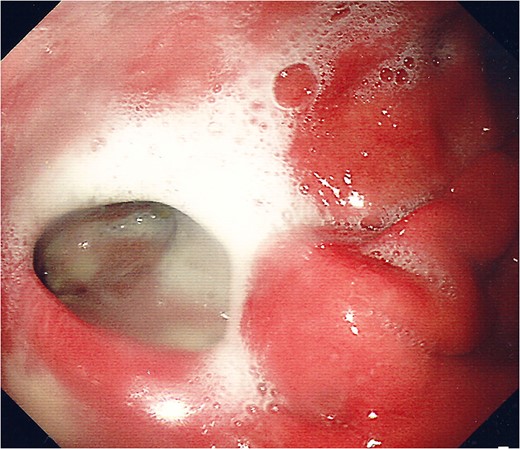

For management of this oesophageal perforation and definitive management of her gastric perforation, the patient was referred to the authors’ unit, a tertiary referral centre for upper GI surgery. In the first instance, a water-soluble contrast swallow was performed to assess the status of the oesophageal perforation. This demonstrated no leak of contrast (Fig. 3) and therefore a diagnostic endoscopy under general anaesthesia was performed in order to assess the cervical oesophagus and also the known gastric perforation. This endoscopy demonstrated a healed oesophageal perforation but persistent gastric perforation with established cavity (Fig. 4) containing an existing transabdominal Robinson drain. The cavity was felt to be of a size likely to heal without the need for further negative pressure vacuum therapy, so a T-tube was placed across it. The established track of the existing abdominal drain was used to guide placement of the T-tube. A nasojejunal feeding tube was placed under vision.

Water-soluble contrast swallow study demonstrating free flow of contrast from oropharynx to stomach with no evidence of leak.